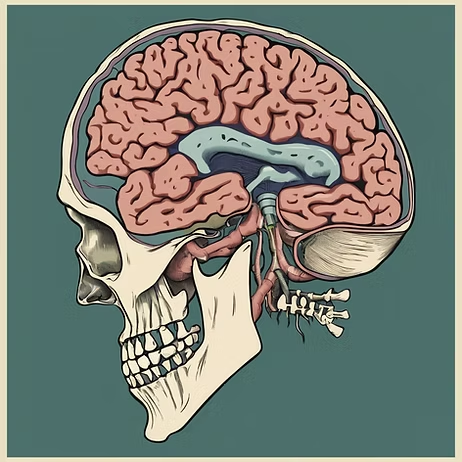

ADHD and

Medicinal Cannabis

Neurodiversity

Management

Understanding the basics of ADHD and Autism

Brain Spectral

Scanning

Learn about brain scans for mental health

Dr Bryce offers one of a kind advances in his field of medicine. He is dedicated to supporting his patients and improving understanding of new and emerging treatments and technologies in a world of ever growing complexity.